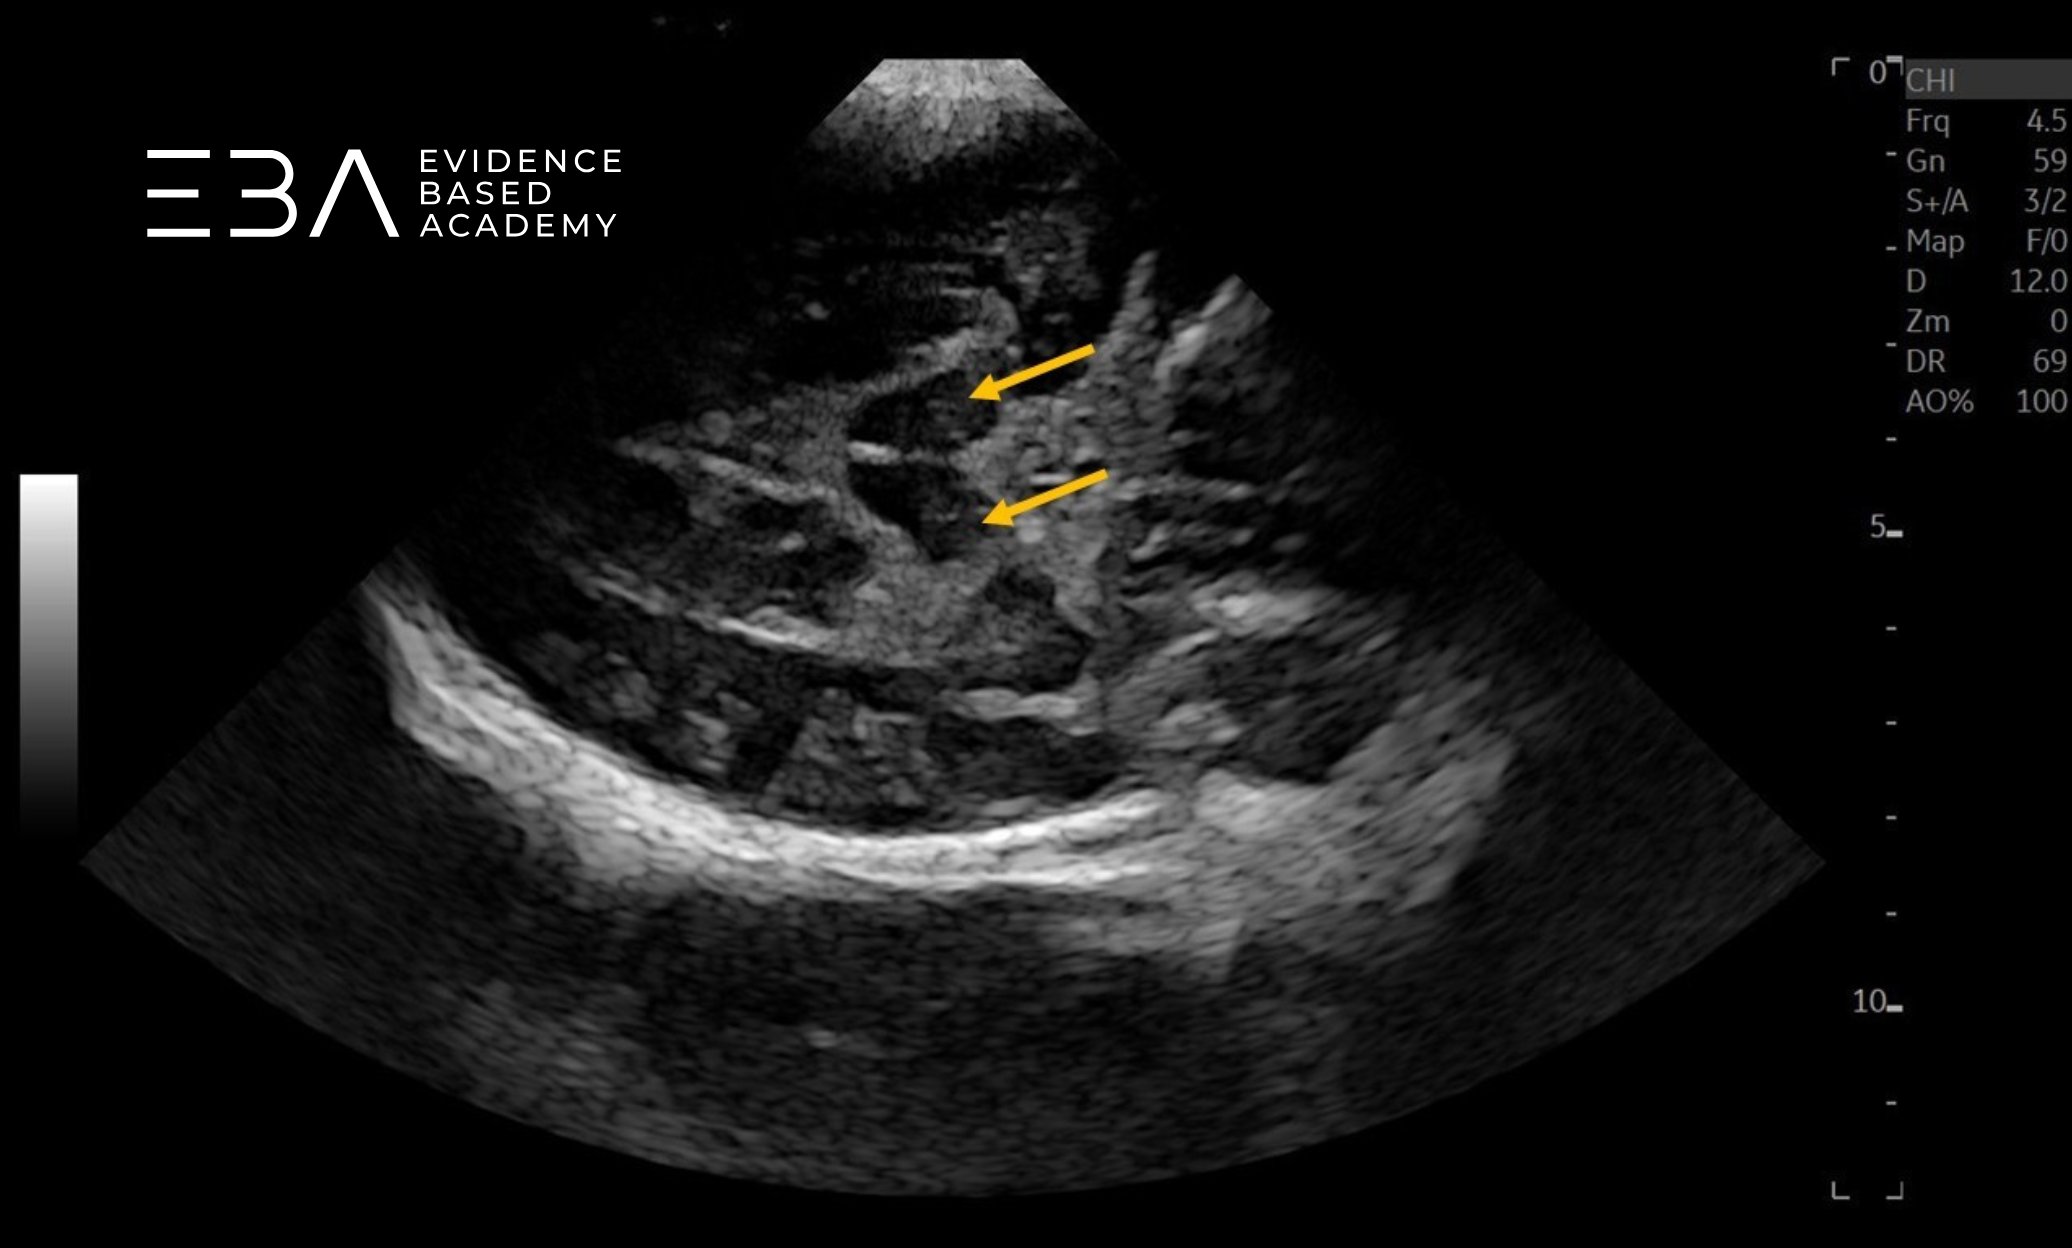

zdj. 0

Głowica sektorowa. Strzałkami zaznaczono półkule móżdżku. Słaba jakość obrazu struktur położonych blisko głowicy.